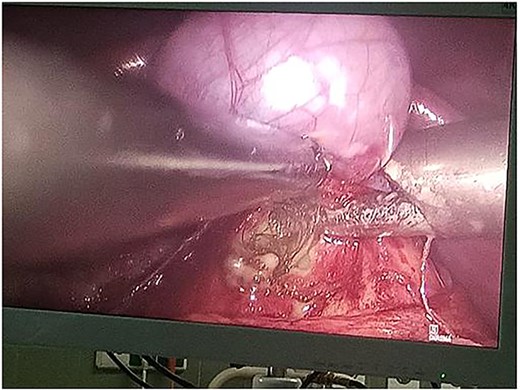

Following multidisciplinary consultation, the lesion was diagnosed as an E. granulosus hydatid cyst. Laparoscopic resection was planned (Fig. 2). Intraoperatively, surgeons suspected the cyst might represent a teratoma. Resection was performed under vascular clamping, with the cutting plane passing through healthy tissue, ensuring complete removal of the cyst wall (Fig. 3). The surgery was uneventful.

Intraoperative laparoscopic view demonstrating dissection of a hydatid cyst located in the caudate lobe of the liver. The cyst, consistent with an atypical type IV Echinococcus granulosus hydatid cyst, shows a well-defined, calcified wall. Atraumatic graspers are used to carefully mobilize the cyst from surrounding hepatic tissue near the hepatic hilum.